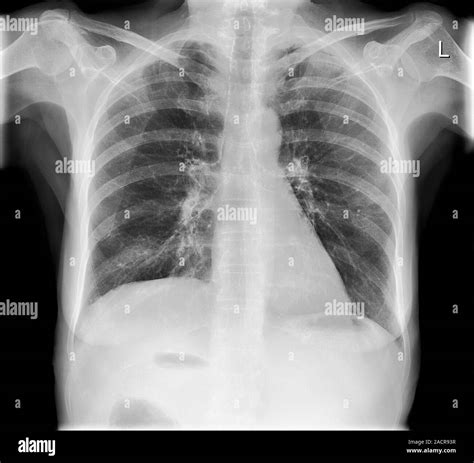

Diagnosing calcification in lungs involves a combination of medical history, physical examination, and diagnostic tests. Some of the common diagnostic methods include:

• Chest X-ray: A chest X-ray can reveal the presence of calcium deposits in the lungs.